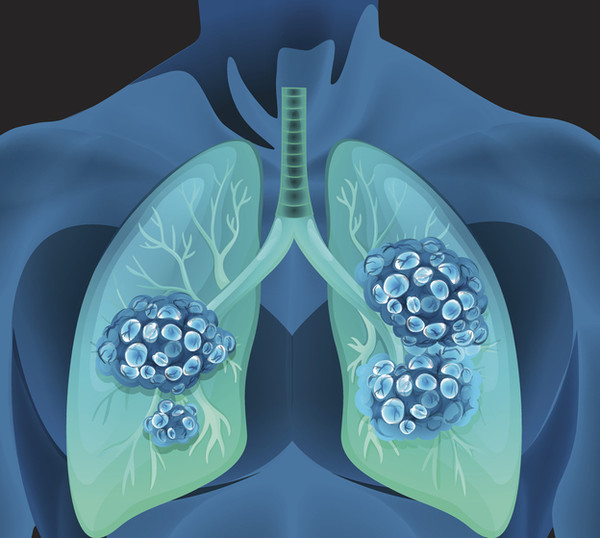

폐암 예방법

흡연을 하지 않더라도 폐암을 걸리는 경우가 있는데 이런 상황을 막기 위한 예방법에는 먼저 요리를 하실 때는 연기를 실내에 들고 있는 것보단 환기를 하셔서 내보내 주는 것이 중요합니다.

그리고 조리 방법으로는 굽거나 튀기는 것보단 찌거나 삶아서 요리하시면 좋으며 구우실 때는 타지 않도록 해주시기 바랍니다. 음식이 타면 발생하게 되는 유해물질이 있는데 그것을 그걸 흡입하게 되면 폐암의 원인이 될 수 있습니다.